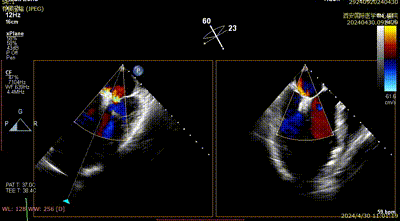

患者为75岁女性,因间断性心慌气短8个月,加重两月入院,既往腔隙性脑梗塞,乳腺癌30年,已治愈。心脏彩超提示:前叶长度:2.9cm,后叶长度:1.2cm,瓣口面积:4.5cm²,病变宽度:13mm。

心脏瓣膜介入团队术中在2区植入一枚二尖瓣夹,关闭二尖瓣夹时时刻关注瓣叶张力,并随时释放张力。患者术后反流降至1+,跨瓣压差为3mmHg。

Case 2影像资料

二尖瓣夹捕获瓣叶

二尖瓣夹夹闭

术后二尖瓣反流评估